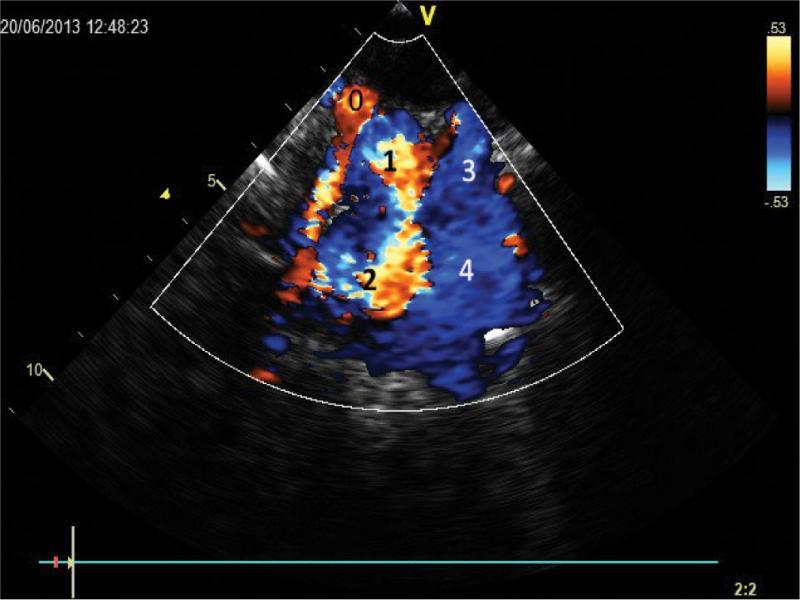

Cross-section showing the upper mediastinum in an inclined plane close to the plane where the aortic arch passes. Visible distal transverse portion of the arch (1) and the initial segment of the descending aorta (2). Systole. The scale of representation of flow velocities with color is adjusted to the visualization of relatively low velocities (max. 53 cm/s, so the aorta is filled with mosaic color dominated by blue (downward flow). A wide vessel (3) runs laterally to the left and posteriorly from the aorta, with a continuous downward flow much at a velocity considerably lower than in the aorta. The inferior segment of the vessel (4) crosses the thoracic aorta posteriorly; the further course of the vessel cannot be traced. Multiple color artefacts caused by proximity to the vessels of aerated lung tissue (0)